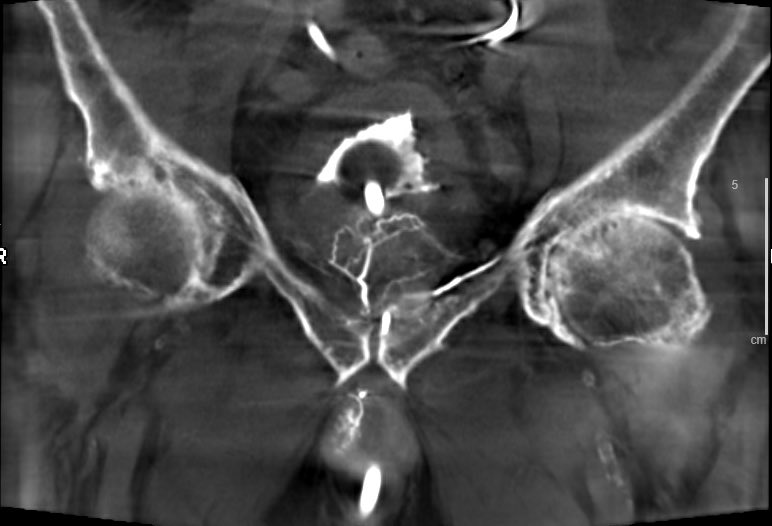

Nice example of multiple feeders to large prostate: yellow-main prostatic artery, orange-distal int pudendal (pena cava), teal-retropublic branch of obturator, pink-distal sup vesical. (Colors courtesy of GE) @SIRRFS @SIR_ECS @StreamMeeting @UsaProstate